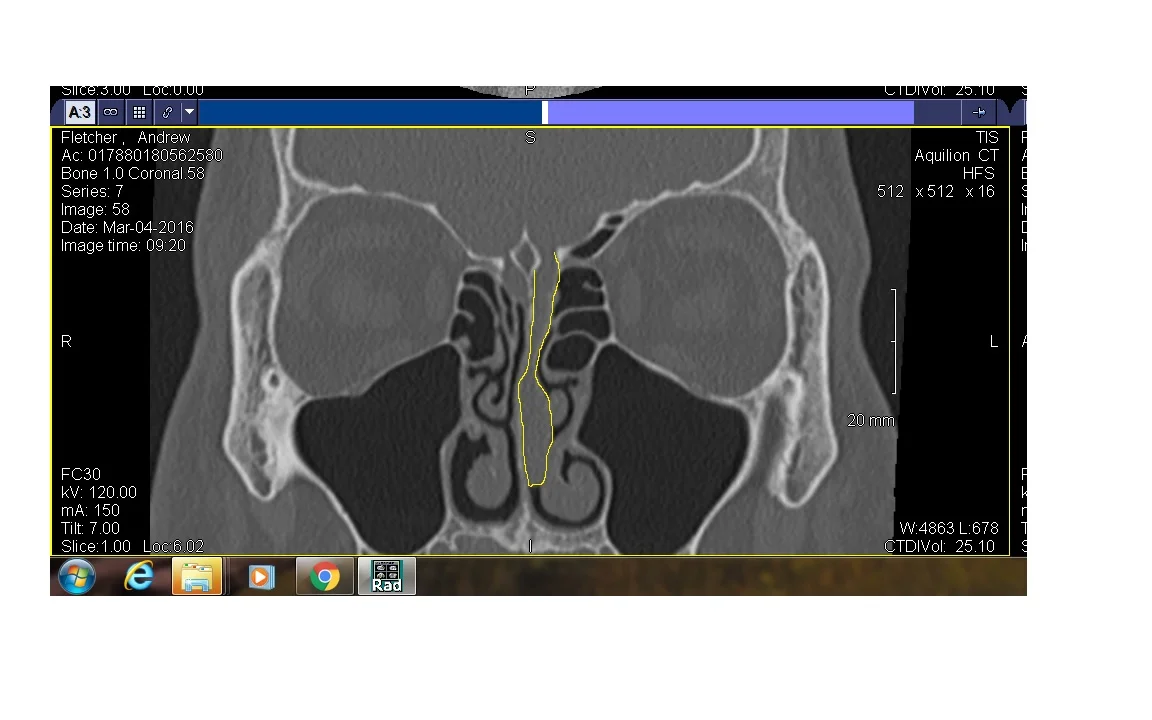

On the radiographs, it looks like a mass. Here is a clip of the MRI. I outlined the tumor in yellow. You can see that I outlined it as it hangs down from the roof of my sinus. If you look at the little yellow arrow, it points to a curvy dark black space that rides alongside the middle of my sinuses. That dark black space is my airway on the right sinus.

My tumor completely fills my left sinus air space, but its not attached to the walls, just the top (dangling like a chandelier).

Yellow outline of Long skinny tumor

As you may or may not know, I had a large tissue growth removed from my left sinus last week. Dr. Whang (for any of you that read things phonetically, it's pronounced Wong...that should take care of my friends that like to be silly like me) removed the majority of that growth last Friday(5/6/16). See the scan on the left.

The surgery was super easy. I stayed awake and because it had been diagnosed previously by biopsy as a benign non-tumor, we chose to leave a small percent of the growth behind. If you look on the scan, you will see this growth starts very high in my nasal cavity and attaches to the bone at the base of my brain. By not removing all of the growth, the surgery was less traumatic and not as risky because the bone between my sinus and brain is very thin. I was totally cool with that decision!